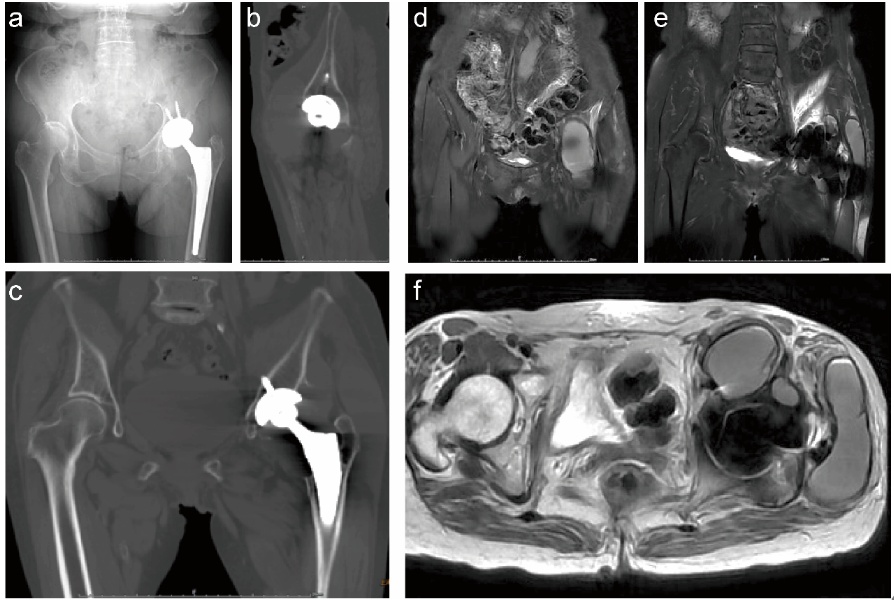

来到瑞金医院骨科后,何川主任医师先通过详尽病史询问和体格检查初步判断,随后安排实验室检查,结果显示炎症标志物、凝血功能均无异常,关节滑液细菌培养也呈阴性;医生没有停下排查的脚步,紧接着安排了X光片和CT检查,影像片上小转子周围的骨溶解现象清晰可见(图1a-c)。“常规影像只能看到骨组织的异常,但没法明确周围软组织的情况。” 随后,减伪影磁共振成像(MRI) 检查显示T1、T2加权像呈现特殊信号混合影(图1 d-f)。

图1:患者影像图